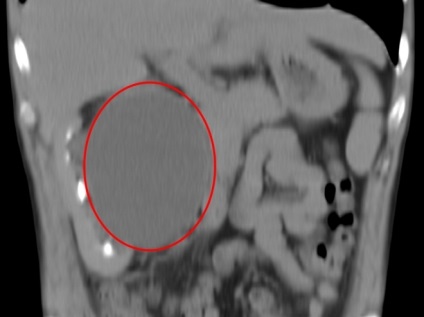

- chisturi renale Patologie sunt considerate a fi anormală creșterea acestuia în dimensiune. Medicina, există cazuri în care chisturi parenchimatoase a ajuns la 10 cm sau mai mult în diametru. chist parenchimul renal lăsat ce este, atunci când tumora este crescut? La această dimensiune a chistului garantat perturba organele interne, ceea ce duce la inflamații și boli infecțioase ale cavității abdominale.